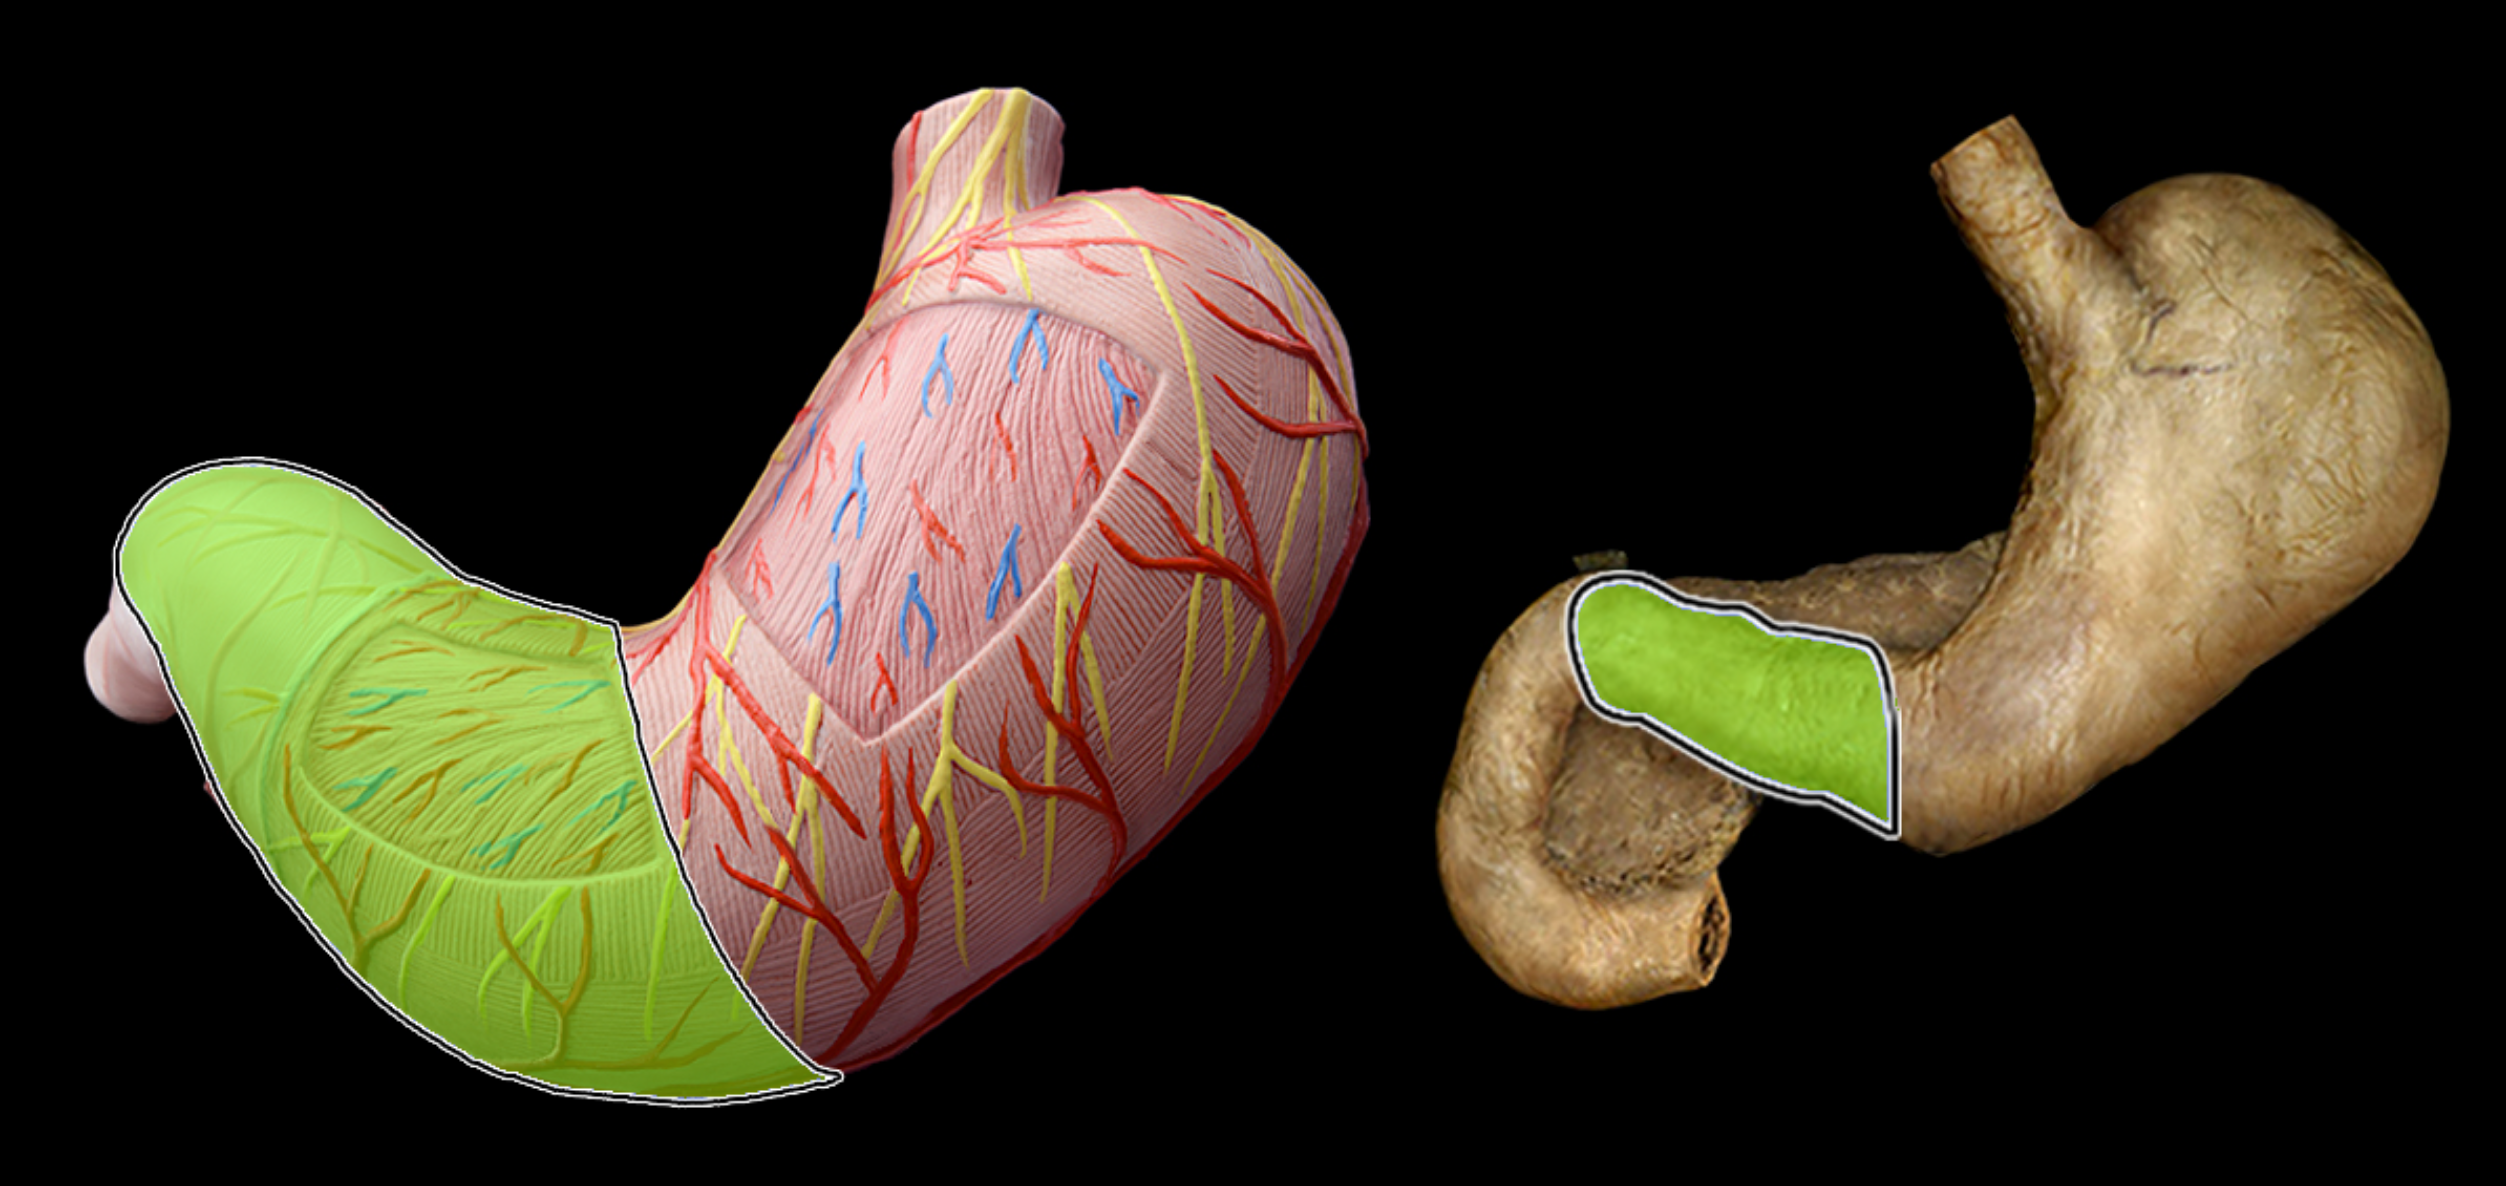

Pyloric part of stomach

Fundus of stomach

cardia of stomach